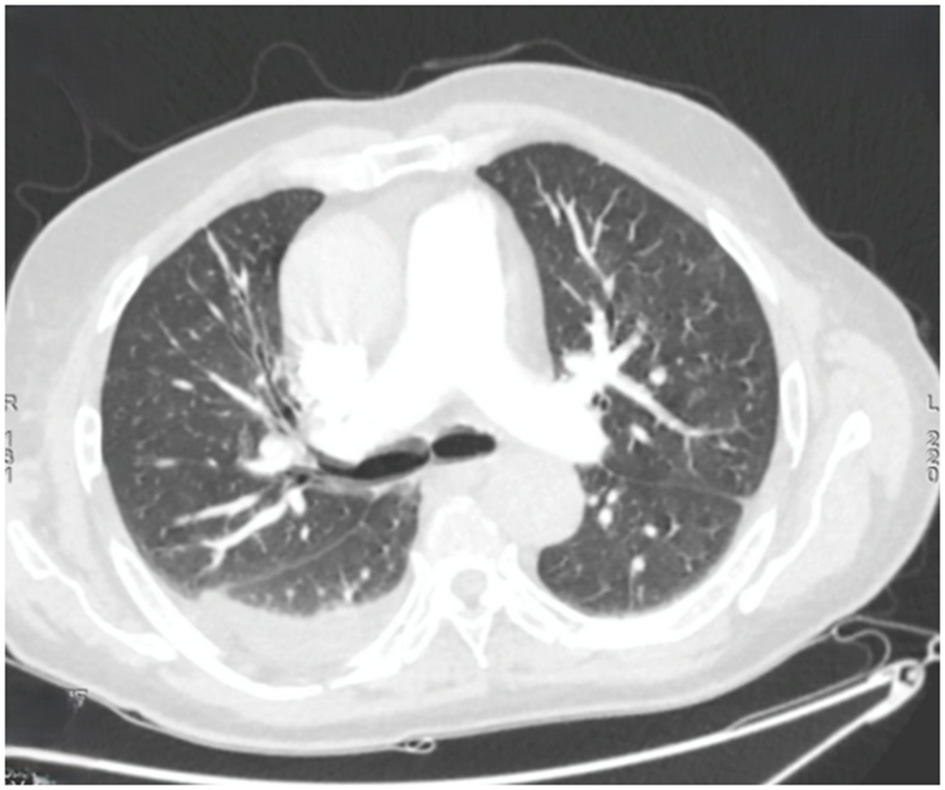

Within 48 h, the patient experienced acute respiratory distress characterized by tachypnea (respiratory rate: 30/min), use of accessory muscles, and oxygen desaturation to 89% on room air. The hypoxemia resolved promptly with low-flow oxygen therapy at 2 L/min via nasal cannula, permitting discontinuation of supplemental oxygen within 24 h. Thoracic computed tomography (CT) demonstrated right posterobasal consolidation and bilateral ground-glass opacities, with no evidence of pulmonary embolism (Figure 2).

Figure 2

Axial chest computed tomography showing multiple bilateral ground-glass nodules, predominantly in the left upper lobe. Bilateral band-like subpleural opacities suggestive of ventilatory abnormalities are noted. A posterior basal consolidation is present in the right lung. Moderate right-sided and mild left-sided pleural effusions are identified, each associated with ipsilateral compressive atelectasis.